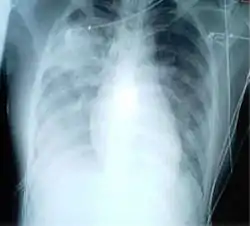

صورة إشعاع صدرية لالتهاب رئوي في الجهتين اليمنى واليسرى.